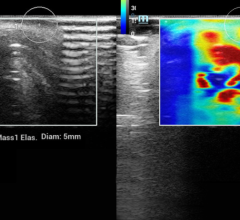

August 6, 2009 - The use of digital breast tomosynthesis and full-field digital mammography (FFDM) combined may be associated with a substantial decrease in recall rate, according to a study performed at UPMC in Pittsburgh, Penn., published in the American Roentgen Ray Society.

An estimated 10 percent of women in the United States are recalled for a second mammogram after an abnormality is detected on the first one. Some researchers believe that digital breast tomosynthesis depicts the breast tissue in a way which may allow radiologists to identify some tumors which could be missed with standard two-dimensional mammography.

In the study, 125 patients were evaluated using a combined method of digital breast tomosynthesis and standard digital mammography. The use of digital breast tomosynthesis and FFDM was associated with a 30 percent reduction in recall rate for cancer-free examinations that would have led to recall if FFDM had been used alone, reported Jules H. Sumkin, M.D., one of the authors of the study.